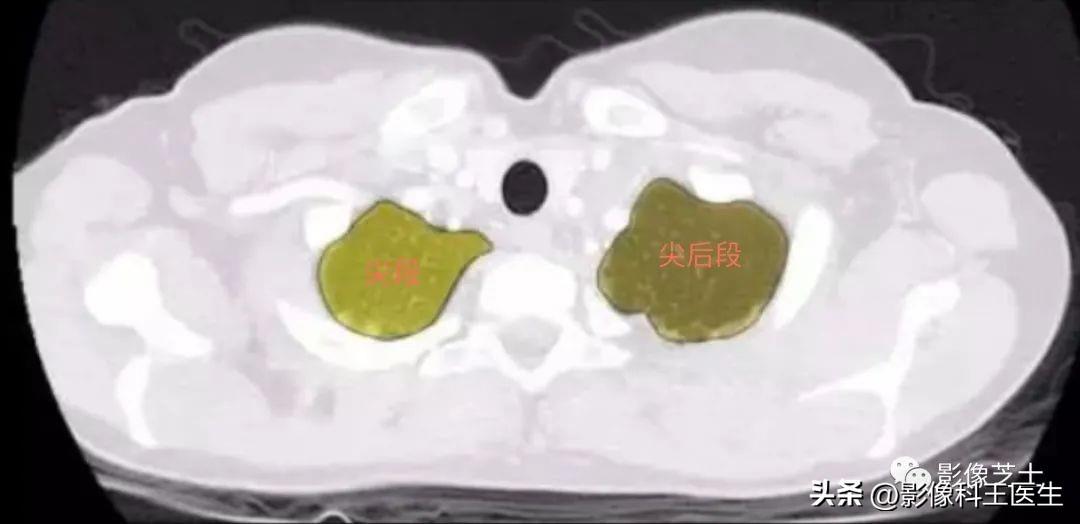

肺的分段